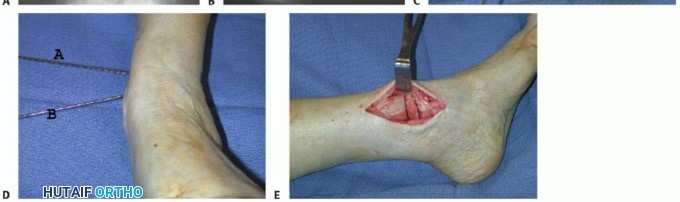

Medial Opening Wedge Supramalleolar Osteotomy

Again, the osteotomy is ideally located at the level of the CORA (TECH FIG 2). If the CORA is located at the ankle joint level or if only minor correction is required and translation of the distal segment is of little concern, then we perform the osteotomy 4 to 5 cm proximal to the medial malleolar tip.

We perform either a horizontal or slightly oblique (proximal medial to distal lateral) tibial osteotomy with a broad oscillating saw, preserving the opposite cortex and periosteal sleeve to serve as a fulcrum for the opening wedge and to enhance stability. If translation is necessary (the osteotomy is intentionally performed at a level different than that of CORA), then the opposite cortex is cut completely to allow the distal segment to move.

Under fluoroscopy, gently distract the tibial osteotomy using a lamina spreader or alternative distraction system until desired correction is achieved.

We routinely use contoured structural graft (generally, the neck portion of a femoral head allograft) to fill the osteotomy.

After correcting the deformity, provisionally fix the osteotomy with Kirschner wires in a manner that does not interfere with the

definitive fixation. Assess the alignment using fluoroscopy, both in the AP and lateral planes.

TECH FIG 2 • Medial opening wedge supramalleolar osteotomy. A. Using a preoperative radiograph, the center of rotation of angulation (CORA) is located at the intersection of two lines that represent the mechanical axes of the proximal and distal segments. B. Under fluoroscopy, a Kirschner wire is used to mark the osteotomy site at the CORA level. C,D. Under fluoroscopy, the tibial osteotomy is gently distracted using a lamina spreader until desired correction is achieved. (A,C,D: From Myerson MS. Osteotomy of the tibia and fibula. In: Reconstructive Foot and Ankle Surgery. Philadelphia: Elsevier, 2005:254.)